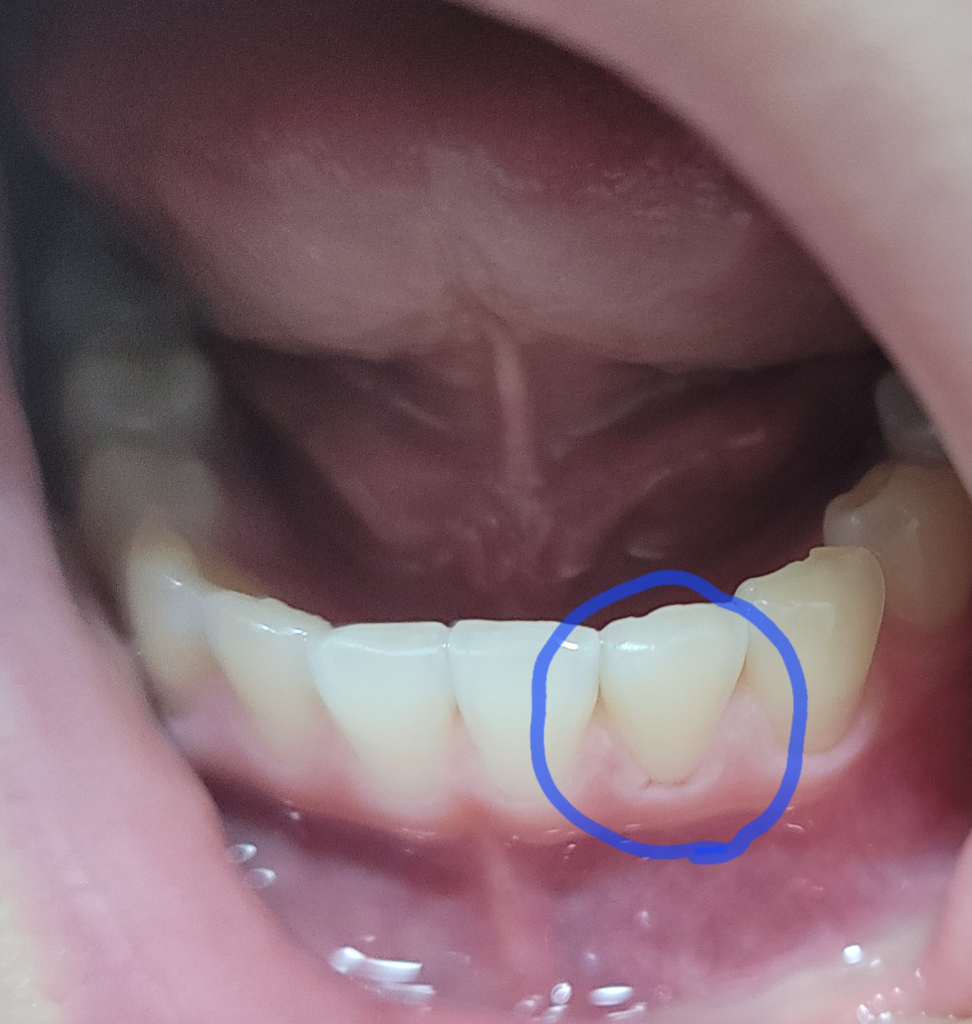

아랫니 잇몸이 ㅠㅠㅠㅠㅠㅠㅠㅠ

왜 혼자만 저렇게 파였죠?ㅠㅠ 아파요..음청 ㅠㅠ 치과 가려면 월요일까지 기다려야 하는데 쟤 왜저래요 ㅠㅠ 너무 아파요 밑에 턱까지 아파와요ㅠㅠ

잇몸이 약해진건가요? 요즘 아랫니들이 좀 아픈데 ㅠㅠ 그래서 스케일링까지 받았는데 2주가 지나도 통증이 안없어져요ㅠ 아쿠아픽 때문에 저럴 수도 있나요? 근데 진짜 너무 아픈데 저기

치석때문에 스켈링을 하면서 잇몸에 약간 상처가 생긴거 같습니다. 시간이 지나면 괜찮아 지실꺼니 너무 걱정하지 않으셔도 됩니다.